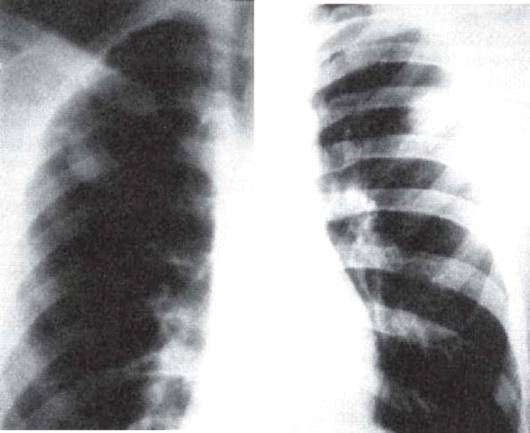

Симптомы и лечение инфильтративного туберкулеза легких

Раздел: Снимки-откровения